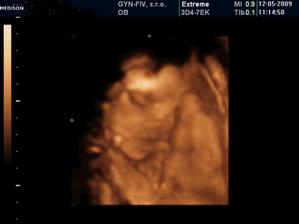

8.3. - 3D UTZ - vraj to bude dievcatkooooooo :o))

21.5. dievcatko potvrdene, tak sa tesiiiiime :o). Vsetko je ok, tak uz nakupujeme vybavicku :o)